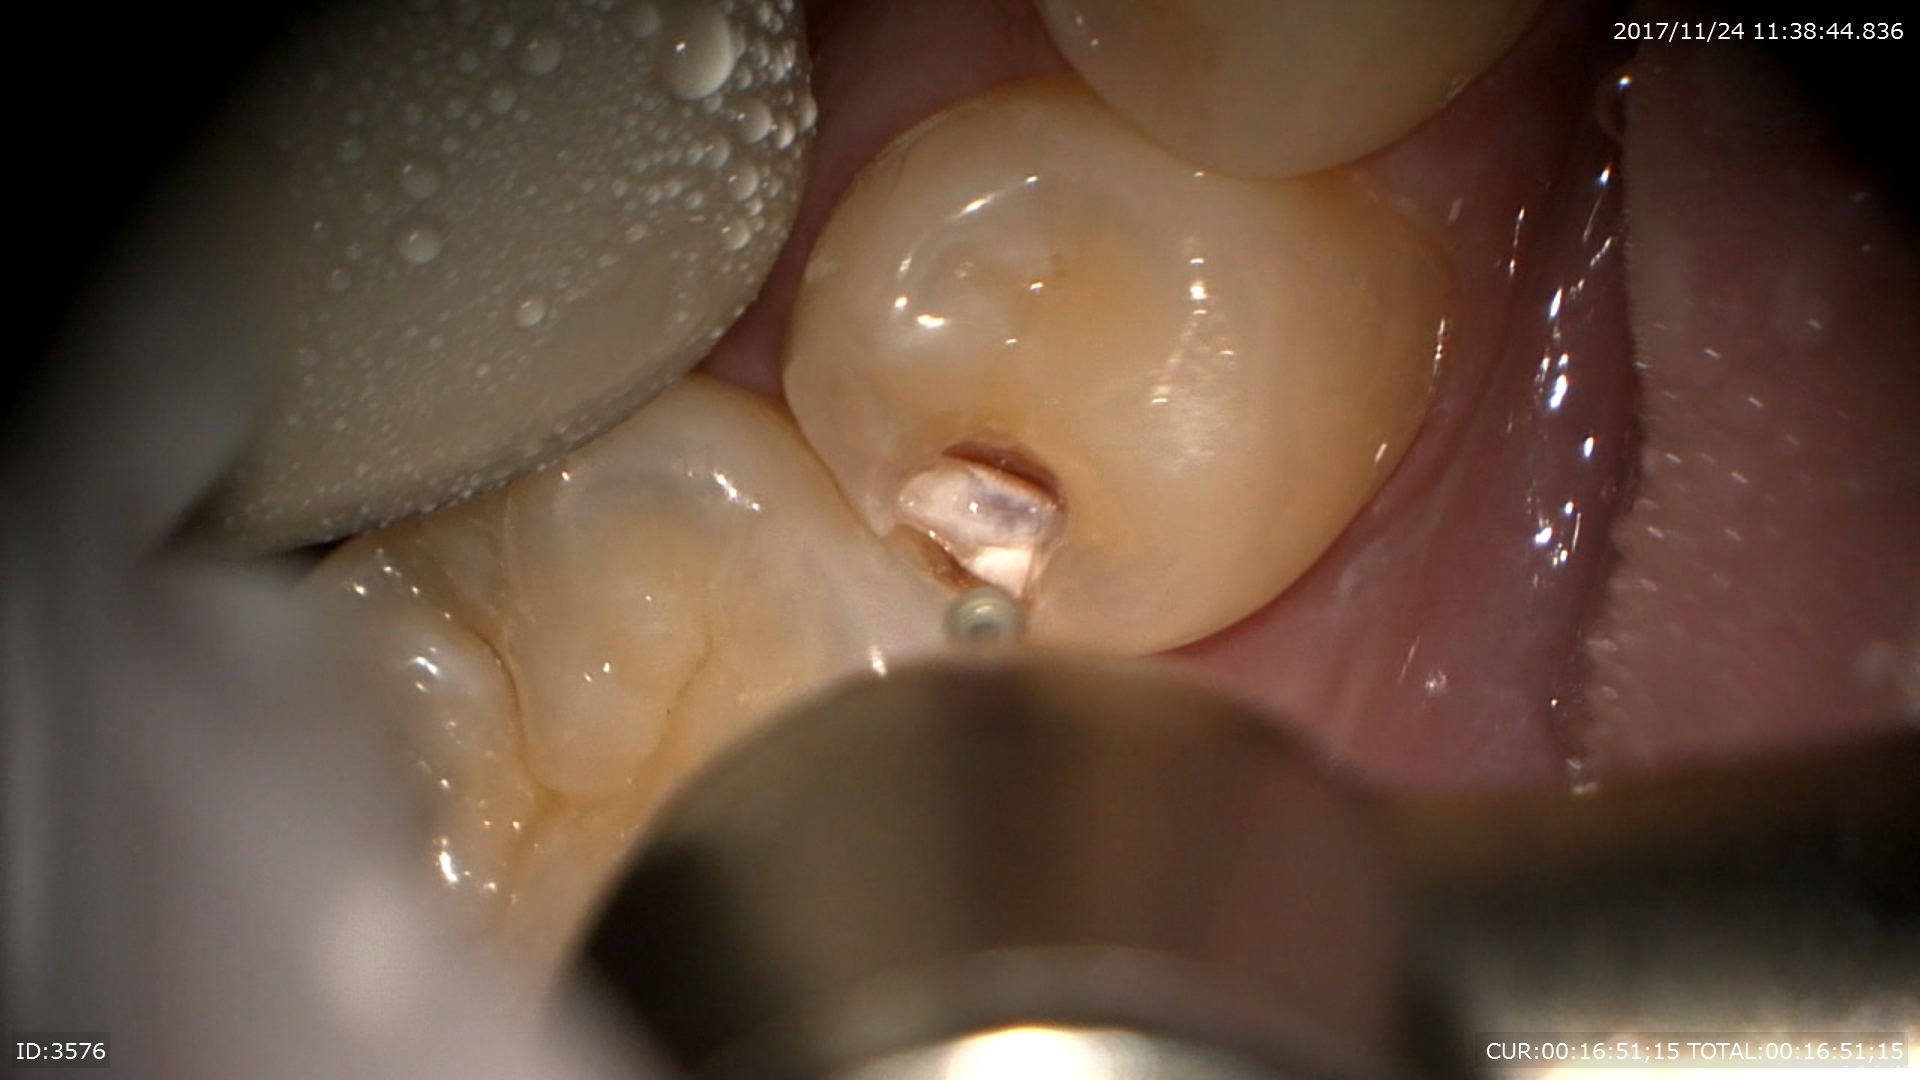

虫歯治療

歯と歯の間に虫歯があります。わかりにくいですよね。

ここです。無痛で行う為のマイクロスコープ。最小限の形成。

早く歯科ドックしてよかったですね。見逃したら神経まで。。。

必ずチェック!!

虫歯用マイクロエキスカで丁寧に。ここを荒く削ると術後痛みます。

神経に近い所はMTAを使用。

2層構造で術後も痛みがないように。

とても丁寧な虫歯治療ができました。